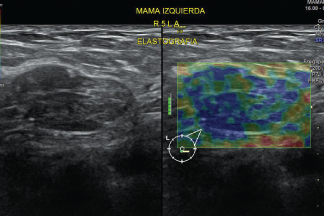

Es un tipo de prueba de diagnóstico por imagen que busca fibrosis. La fibrosis es una afección que se puede producir en MAMA, Hígado, Tiroides y Próstata entre otros.

En EDE Satélite, sabes que esta prueba es auxiliar importante en forma cuantitativa, en la clasificación de un Nódulo simple o complejo, siendo un estudio que ayuda a establecer en forma más óptima la clasificación BIRADS o TIRADS.

Se puede emplear para lesiones Nodulares Mamarias, Tiroideas, Hepáticas, Partes blandas o Músculo Esqueléticas.